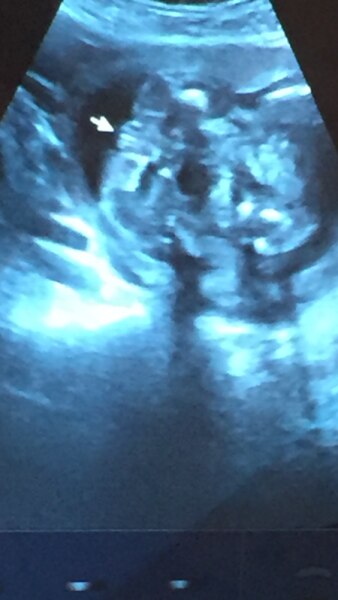

Hallo könnt ihr mir weiterhelfen? Ich habe bereits 2 Jungs jetzt meinten 2 verschiedene Ärzte ein Mädchen zu sehen. Habe sogar ein ,,Beweisfoto" bekommen. :-) letzte Woche hat eine bekannte endbunden bei ihr hieß es bis zum Schluss Mädchen (das vierte) und raus kam plötzlich ein Junge. Und jetzt bin ich total verunsichert. Könnt ihr mal das Foto anschauen was ihr da sehen tut? Vielen Dank im Voraus

Bild zu Geschlechtsouting - Schwanger - wer noch? Rund um die Schwangerschaft

Sieht definitiv nach Mädchen aus. Welche woche bist du ? Lg

Ich finde das Bild ist viel zu unscharf, sorry. Könnte nach dem was ich sehe beides sein... Beim nächsten US kann man es vielleicht sicher sehen. Ansonsten würde ich auf die Ärzte vertrauen. Ja, es gibt Irrtümer, die sind aber sehr selten. LG Lilly

Ich habe 3 Jungs , 1 Mädchen und bin mit dem 4. Jungen schwanger. Auf dem Ultraschallbilder sieht man definitiv ein Mädchen ! Da gibt's keinen Zweifel . Hab da mittlerweile nen geschulten Blick

So ein Bild hab ich von meiner Tochter auch: )